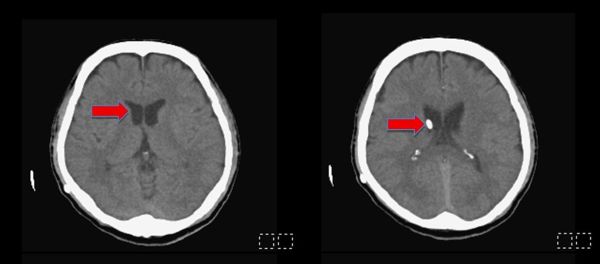

圖一、手術前腦部斷層掃描,發現所有的腦室脹大(紅色箭頭,黑色部份構造)。

圖二、手術後半年,腦部電腦斷層影像顯示,所有脹大的腦室皆已恢復正常大小,可見到所放置右側腦室的導管(紅色箭頭)。